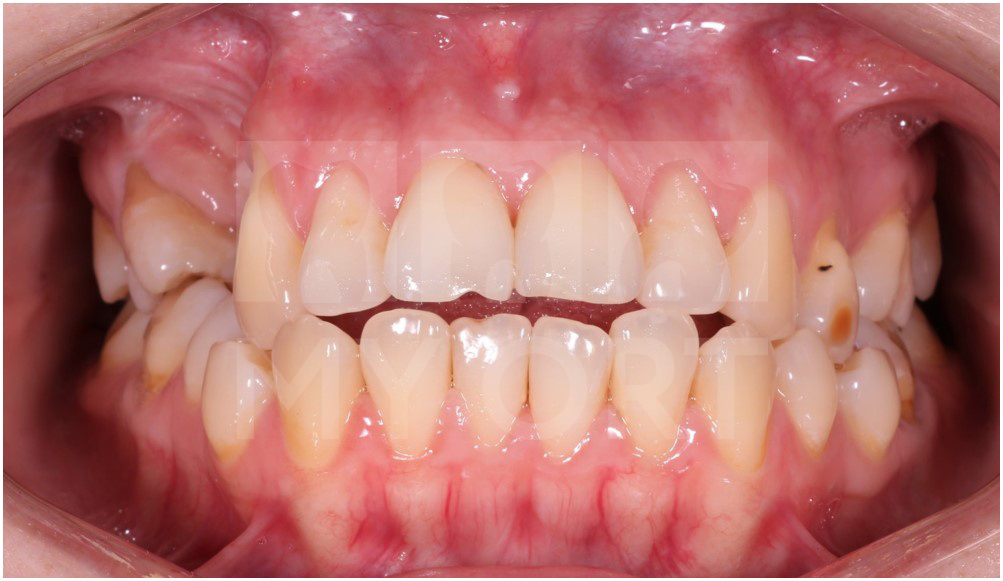

Результат спустя 16 месяцев ортодонтического лечения.

Результат лечения через 16 месяцев